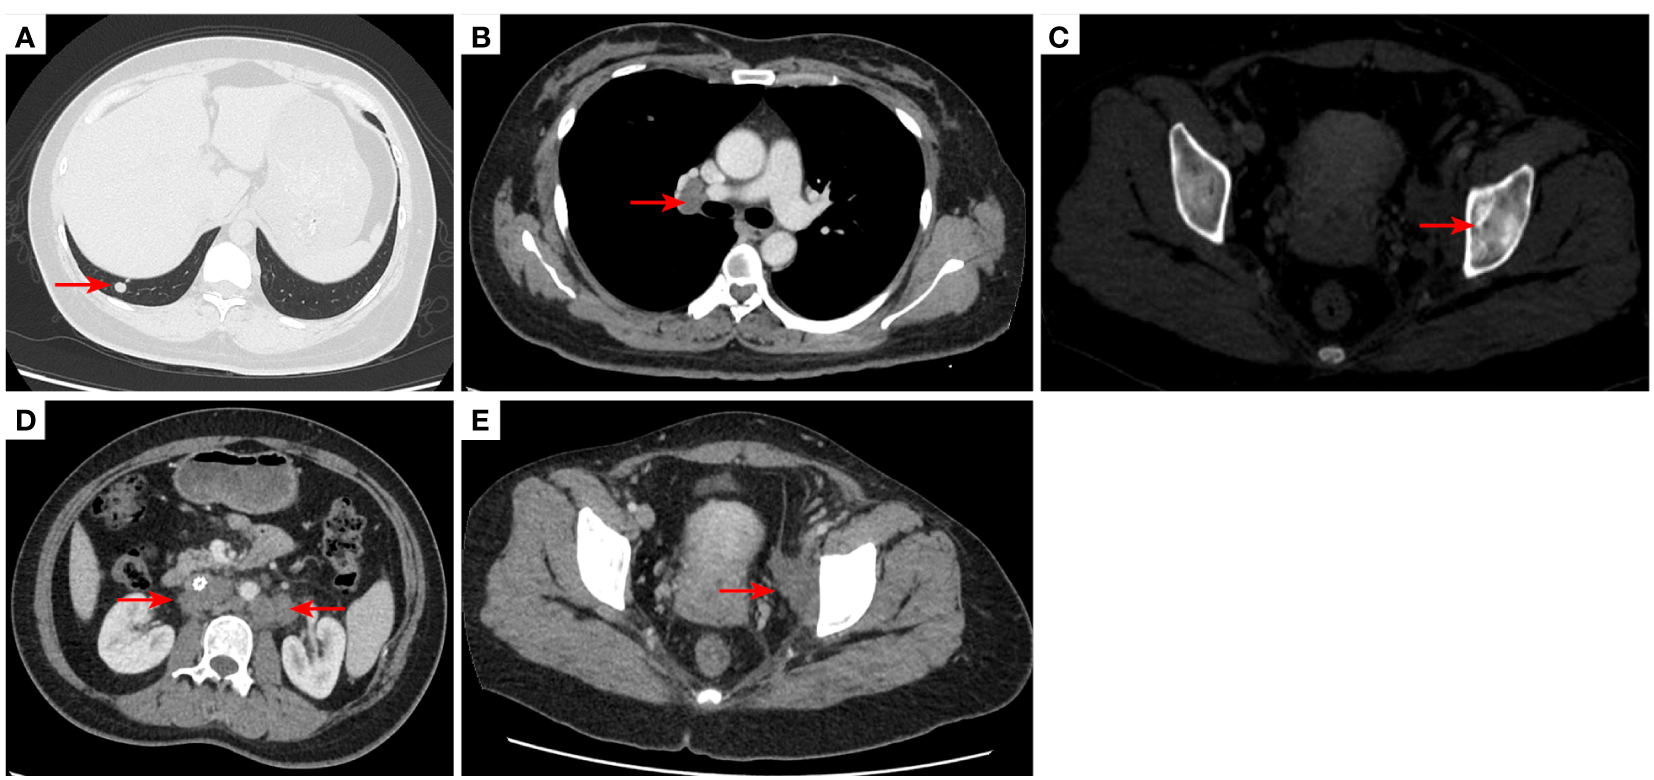

Figure 3

2020–9-16 CT scan: The original metastatic tumor in the right lower lobe of the lung disappeared (A); no enlarged lymph nodes were found in the right hilum (B). Left acetabular metastases [red arrow, (C)]. The short diameter of retroperitoneal lymph nodes was 0.91 cm which was a non-confirmed metastases [red arrow, (D)], and the short diameter of left pelvic lymph nodes was 2.98 cm [red arrow, (E)]. The efficacy was SD. SD, stable disease.